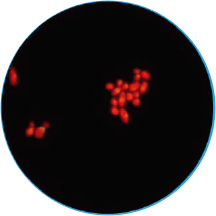

免疫荧光法结果展示及判读示例

阴道分泌物多重免疫荧光染色技术,具备形态学与荧光学的双重优势。可以同时对上皮细胞,白细胞,乳酸杆菌,线索细胞,念珠菌和毛滴虫等进行染色区分,既能检测阴道相关病原体感染,也能评估其阴道微生态和阴道清洁度等是否正常,为临床的快速诊断和治疗提供帮助。

念球菌

橙红色荧光

孢子形态直径3-6 μm

明显大于细菌,小于滴虫